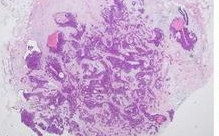

用麦默通或安珂进行穿刺抽出活体送检,进行病理检查以确诊。